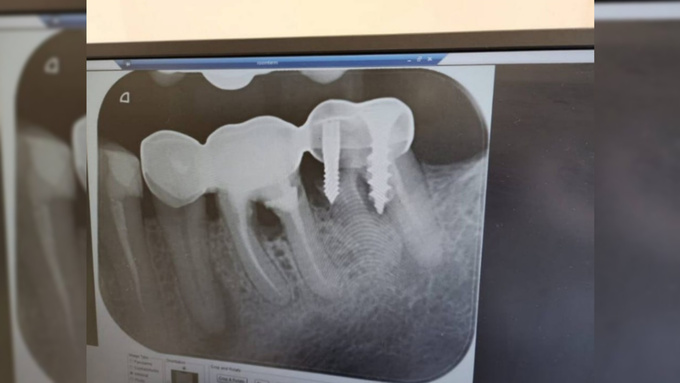

Рентгеновский снимок полости рта / Фото: "Молния. Москва"

Во время приема стоматолог столкнулся с необычным случаем: один из пациентов обратился за помощью. Пациенту сделали рентген. На снимке четко видно, что зуб был механически прикреплен к челюсти с помощью самореза.

Как сообщил сам врач, подобная ситуация произошла в его практике впервые. Саморез пришлось срочно удалять, поскольку металл начал окисляться в полости рта, что могло привести к серьезным осложнениям и воспалительному процессу. Подробности о том, как и почему была выполнена такая "конструкция", не уточняются.